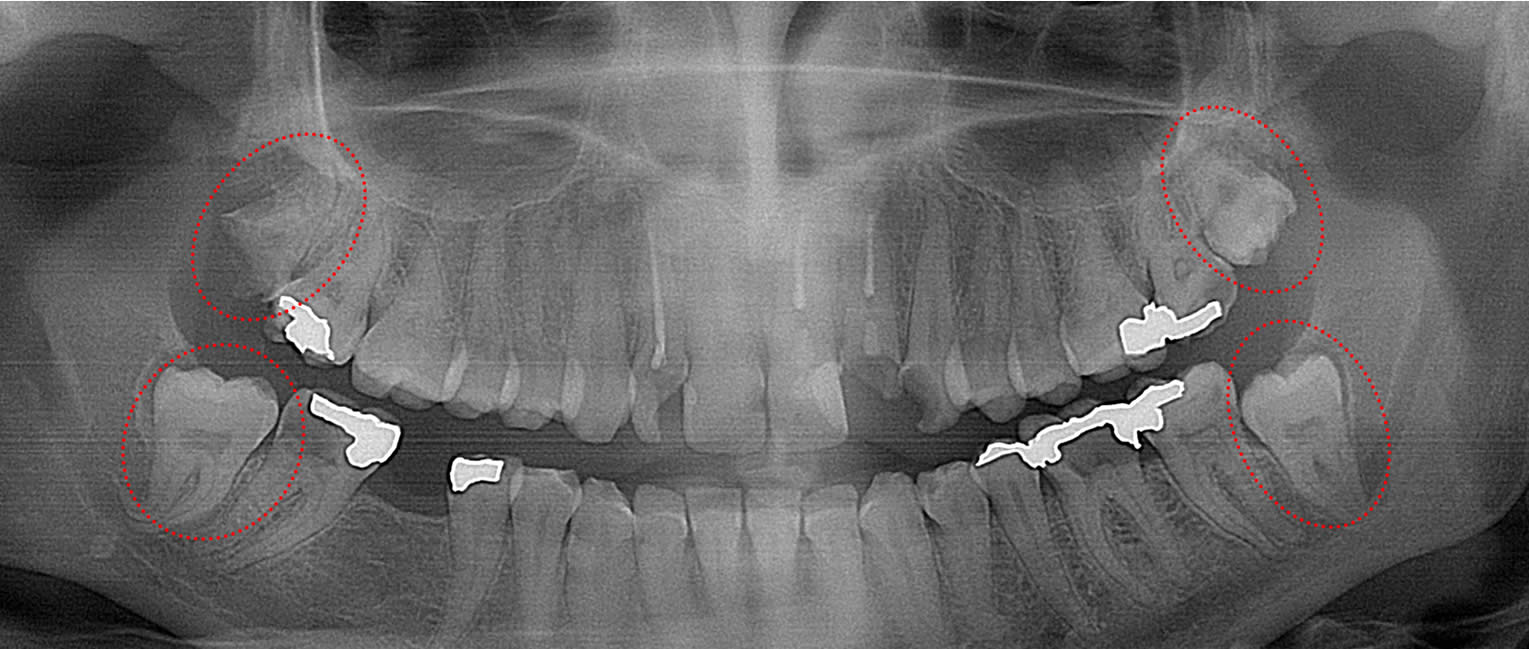

bilateral mandibular 3rd molars present with cysts

This 55 year old patient has bilateral mandibular 3rd molars with cysts forming around them (circled) that is destroying the bone in her mandible. This patient will likely lose her 2nd molars and suffer mandible fractures if the 3rd molars and cysts are not immediately removed.

This study does not include additional complications associated with retained fully impacted 3rd molars, such as cyst formation and other problems that predictably arise with a rate of nearly 60% when there is a bony expansion of more than 2.5 mm from the crown of the impacted molar.27